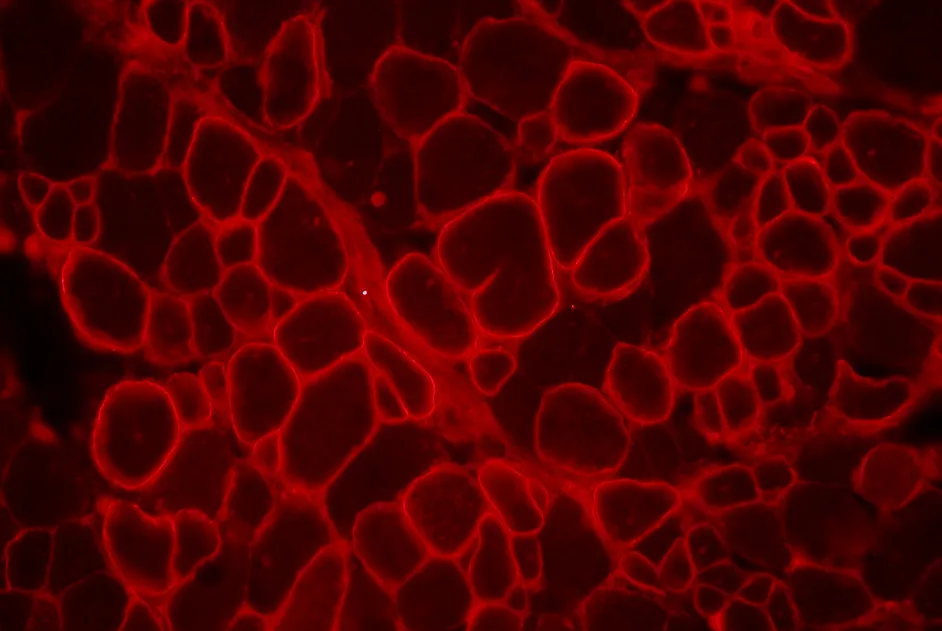

Le compte rendu du 193e workshop ENMC consacré au diagnostic anatomo-pathologique dans la myopathie inflammatoire idiopathique est paru en septembre 2013.